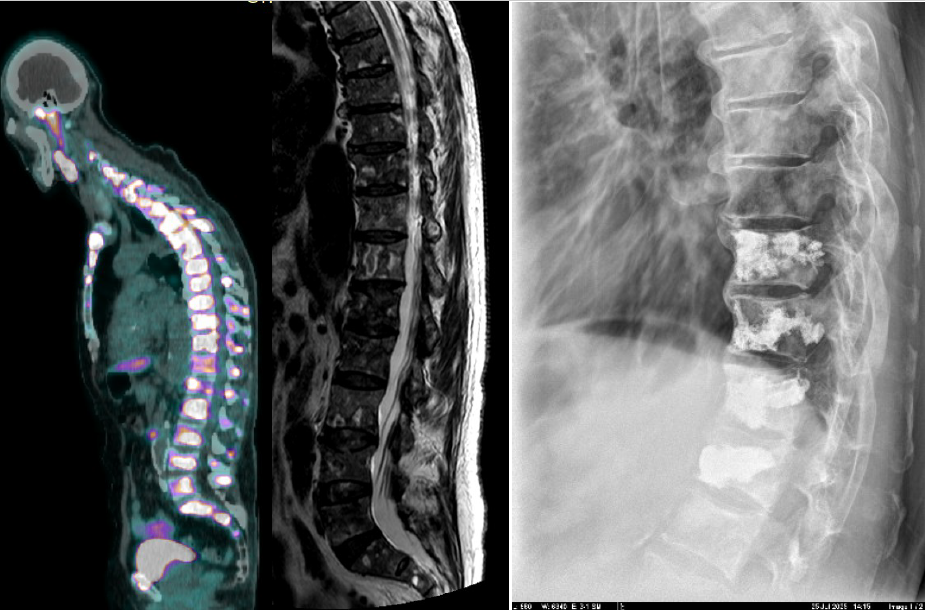

Επίσης αναφέρουμε και έναν πρoσφατο ασθενή με νεοδιαγνωσμένο καρκίνο προστάτη και επώδυνα κατάγματα σπονδυλικής στήλης: εδώ πέρα από το πρόβλημα της ρύθμισης του άλγους του ασθενούς υπήρχε και διαγνωστικό πρόβλημα αφού δεν ήταν σαφές αν τα κατάγματα οφείλονταν σε οστεοπόρωση (λόγω ηλικίας και αντιανδρογονικής θεραπείας) ή ήταν μεταστατικά: έγινε λοιπόν ΚΦΠ 4 σπονδύλων (Ο1, Θ12, Θ11, Θ10) και ταυτόχρονα βιοψία με πολύ καλά αποτελέσματα και πλήρη ίαση του άλγους του ασθενούς ενώ διαπιστώθηκε ότι η αιτία ήταν η μεταστατική νόσος (και έτσι έγινε η ανάλογη τροποποίηση της αγωγής από τον θεράποντα ογκολόγο).

Εδώ παραθέτουμε αριστερά το PET scan που δείχνει και την κυφωτική στάση του ασθενούς, στην μέση την μαγνητική με τα πολλαπλά κατάγματα ιδίως στην θωρακοσφυικη μοίρα και την ακτινογραφία 6 μήνες μτχ.